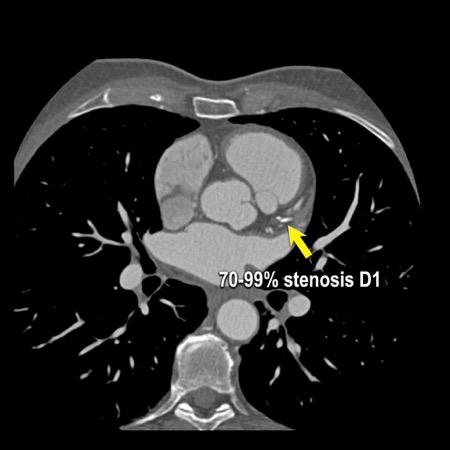

The findings are:

artefacts. - Calcified plaque in

the D1 causing severe stenosis (70-99%) at the origin (white arrows). - Partially calcified

Due to severe stenosis in D1, extensive plaque burden, some

non-diagnostic segments and a stent this patient classifies as CAD-RADS

4A/P4/N/S, which means that this patient needs further workup.

The ICA shows some wall irregularities to a maximum of 30% stenosis in

the proximal LAD.

The D1 shows 50% stenosis at the origin (black arrows). The LCX shows some wall